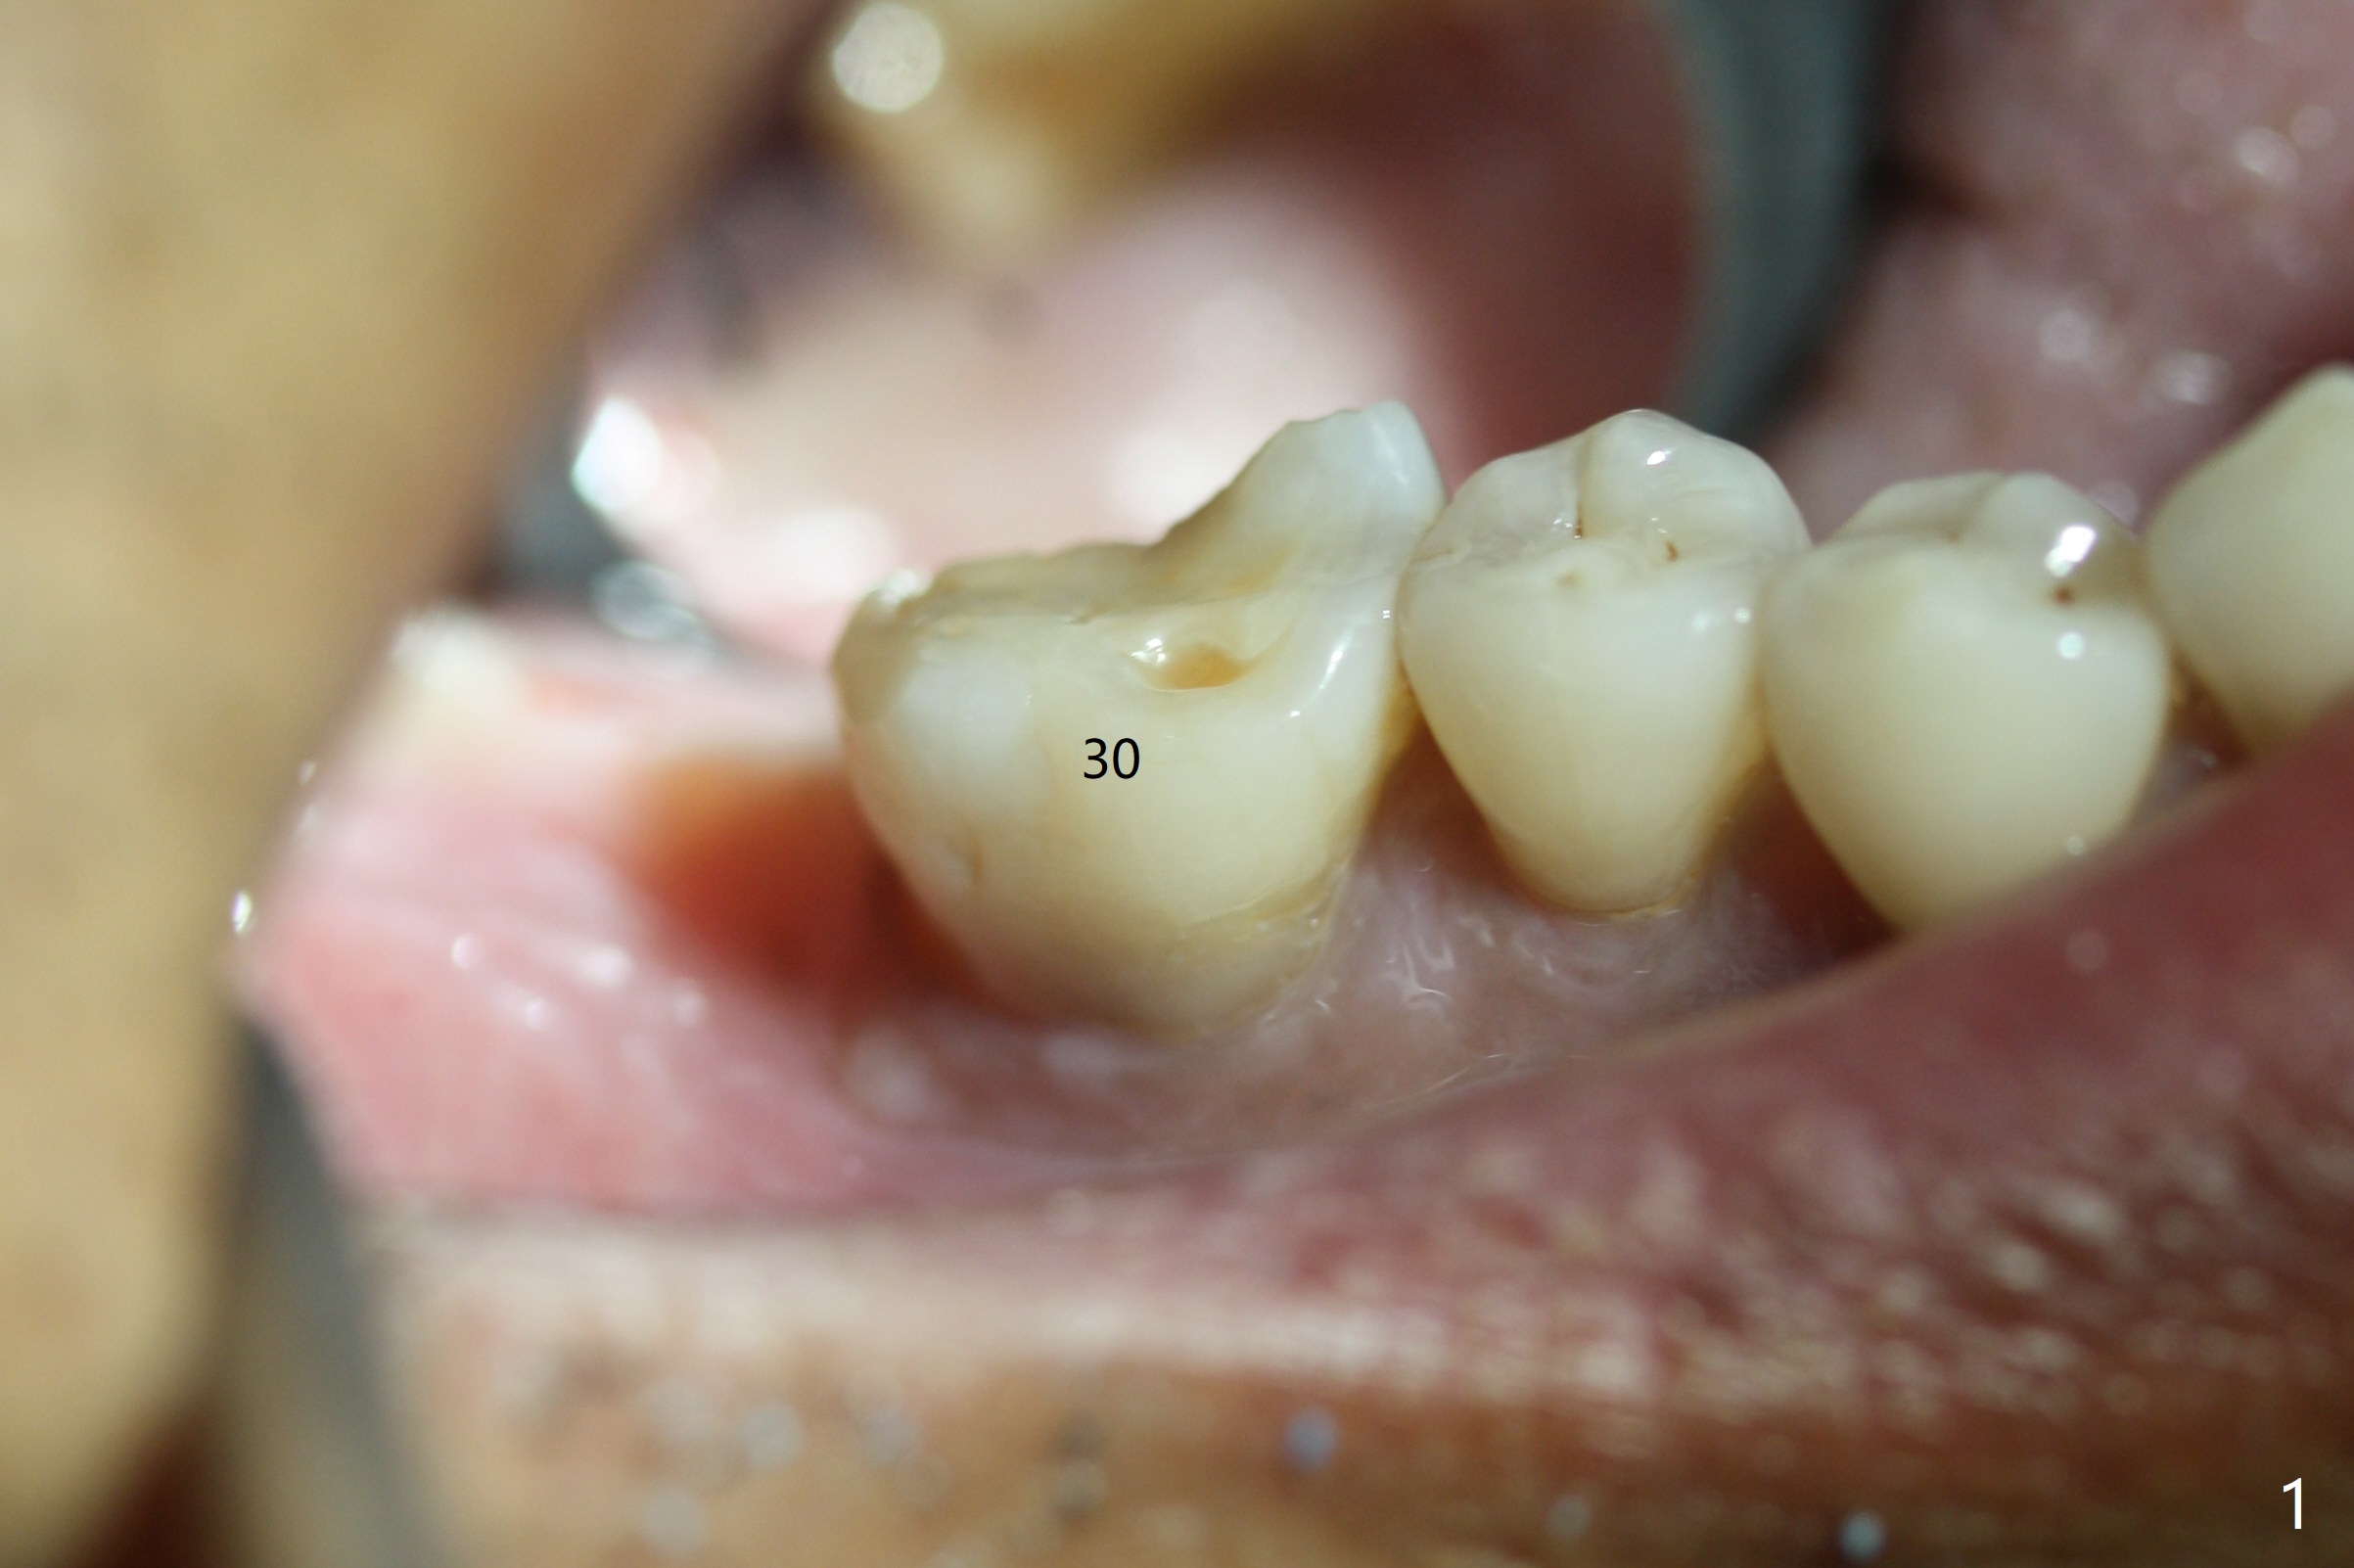

Abutment vs. Definitive One

After extraction of the tooth #30 with lingual subgingival fracture (Fig.1), the septum is fairly large (Fig.2 S). A bony vertical anchor pin (Fig.3 *) is inserted in the septum following pointed drill to to stabilize the guide during osteotomy and implant placement of #31. When the latter is finished, a fixture anchor pin is used at #31 as planned. A healing abutment is placed at #31 because of supraeruption of the tooth #2 (Fig.4,5), while a cementation abutment is placed at #30 (Fig.5) with autogenous bone (from drills) and allograft placed around it (*, Fig.6). Finally an immediate nonfunctional provisional is fabricated to keep the bone graft in place (Fig.7 P). The bone graft remains in place gel-like nearly 1 month postop (Fig.8). CBCT axial section shows that there is not enough space for mini implant placement at the tooth #2 (Fig.9). Restoration-induced intrusion will be conducted using the implants at #30 and 31 three-4 months postop. The buccal gingiva (Fig.10 *) is lingual to the provisional (P) nearly 1.5 months postop. When the provisional is removed, it appears that the mesiobuccal bone graft has lost (Fig.11). Two days later, the cementation abutment is loose and removed; the gingival cuff looks healthy (Fig.12). A 6.8x5 mm healing abutment is placed (Fig.13). In 2.5 to 3 months, abutments will be placed at #30 and 31. Splinted provisional will be fabricated over supraocclusion to intrude the tooth #2 with a stop on the left side. Surprisingly the patient agrees to intrude the tooth #2 with 2 mini implants 5.5 months postop (Fig.14,15). However, the miniimplants dislodged. Due to coronavirus, the implants are restored with heavy abutment and opposing tooth trimming 1 year 9 months postop (Fig.16). Magicore should have been placed instead.